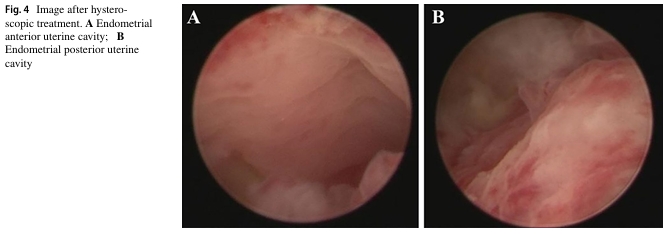

七名患者在术后进行三次自体骨髓间充质干细胞宫腔灌注治疗。两年内进行随访,子宫内膜厚度和基底层血流量均有明显改善,宫腔内形态正常,且均未检查到新的宫腔粘连症状。其中两例患者在术后分别经自然受孕和胚胎移植成功分娩。